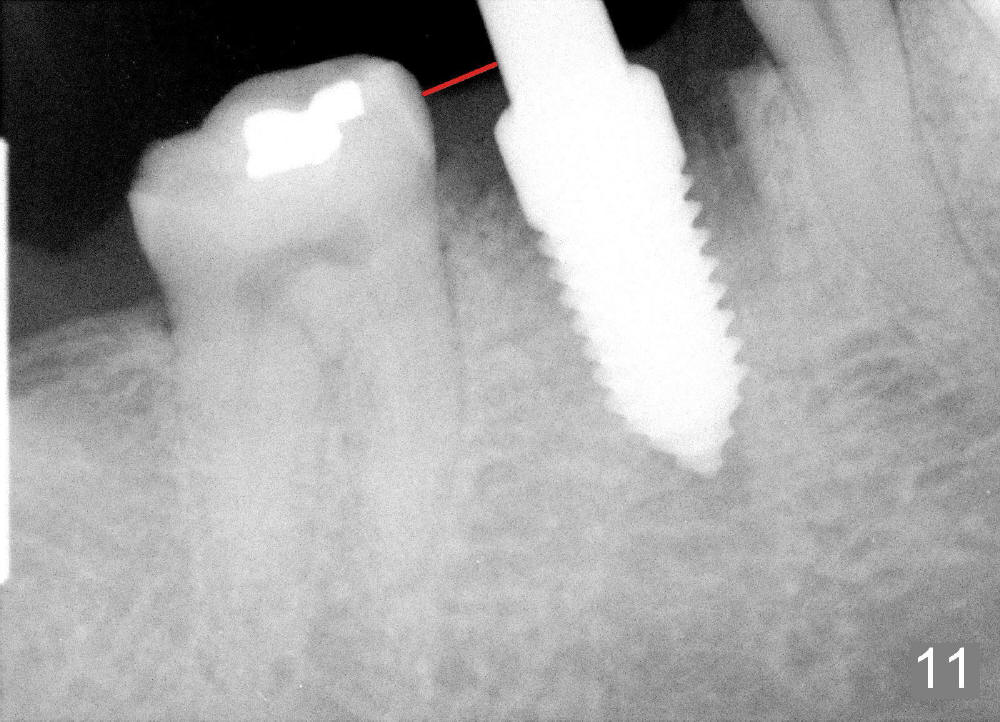

A 38-year-old lady agrees to have implant placement 7 years after loss of the crown of the lower right first molar (Fig.1,2). When the tooth is extracted, the septum is found to be low (Fig.3,4). To confirm it, a PA is taken (Fig.5). To initiate an osteotomy in the septum, it is trans-sectioned with thin osteotomes as shown in Fig.4 insert (black line). A 2 mm pilot drill is placed in the septum (Fig.6: P). The osteotomy is enlarged by 2.5-4.0 mm reamers (Fig.7,8), followed by insertion of 6x17 mm tapered tap at the depth 14 mm (Fig.9). The osteotomy is further enlarged by 4.5 and 5.0 mm reamers. A 6.0x14 mm one piece implant is placed initially. The trajectory is not ideal. A 6.0x14 mm one piece implant is placed initially. The trajectory is not ideal. The implant is removed from the osteotomy partially and reinserted with improved trajectory (Fig.11, compare to Fig.10 (red line)). Primary stability is high. There is not much bone mesiodistally so that the trajectory is easily changed in that direction. After abutment preparation, mixture of autogenous bone (harvested from reamers) and allograft is placed in the residual mesial and distal sockets (Fig.12). To contain the bone graft, an immediate provisional is placed (Fig.13 P). The occlusal plane of the provisional is significantly lower than that of the adjacent teeth to avoid micromovement of the implant. The patient is advised to eat soft food on the left side. Six days postop, the patient returns for prophy. The provisional is removed; the bone graft appears to be incorporating into the socket (Fig.14). After recementation, the provisional remains in place for 3.5 months; PA shows increased bone density in the mesial and distal sockets (Fig.15, compare to Fig.5,11). Due to insurance coverage, the patient defers fabrication of definitive restoration for at least 7 months. The immediate provisional is finally lost 8.5 months postop: the gingiva attaches to the 1-piece implant (Fig.16), while the density of the mesial socket increases (Fig.17 *) with formation of the cortex (lamina dura) coronally (v). Before the provisional (Fig.18 P) is removed for cementation of the definitive restoration, black shadow (*) is noted over the buccal gingiva. It is partially due to buccal placement (Fig.19) and partially due to buccal atrophy over a period of 10.5 months postop. How to prevent buccal placement? Positioning the first pilot drill in the septum buccolingually is a key. Eleven months post crown (Fig.20 C) cementation, the black shadow remains, but there is no tenderness. If the implant threads are immediately underneath the periosteum, there is tenderness.